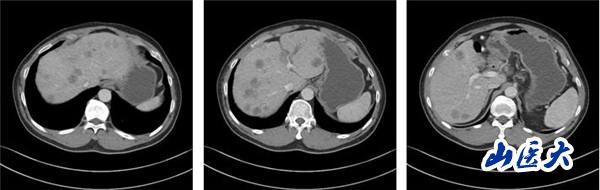

(2022-01-08基线肝脏CT静脉期)

该患者在团队成员仔细阅片、认真讨论下,因患者为PD-L1 CPS高表达人群,TMB-H基因状态。尽管目前国内外胰腺癌诊疗指南并没有对该类型患者指明个体化治疗策略,但通过查阅近年来已经报道的小样本临床研究以及个案报道资料,最终为患者制定了免疫联合化疗治疗策略:PD-1单抗+AG治疗6周期后,PD-1单抗+卡培他滨维持治疗。2022年8月26日,患者再次完善胸腹部CT评价疗效后,达到了大PR(部分缓解)的效果。多达20余处肝转移病灶几乎消失不见,患者可以正常工作生活。